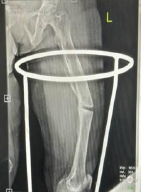

X-rays revealed cystic expansion and cortical thinning [3] of the proximal phalanges with lytic lesions (Fig. 2). Computed tomography imaging confirmed cortical destruction and periosteal reaction (Fig. 3).

Figure 2: X-ray B/L hands showing involvement of phalanx.